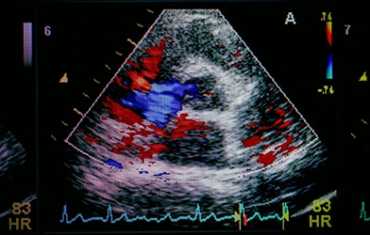

- цветового допплера - ЦДК (для определения направления потоков крови и выявления патологических),

ЭхоКГ-исследование начинают с двухмерной ЭхоКГ в режиме реального времени, которая визуализирует с высокой разрешающей способностью структуры сердца и их движение. Изображение обычно получают из четырех стандартных доступов — парастернального, апикального, субкостального и супрастернального — путем поворота и отклонения датчика. Качественные и количественные измерения площадей и объемов сердца получают в В- или М-режиме. Оценку допплеровского спектра скоростей и цветовое допплеровское картирование проводят, используя двухмерное изображение. Новые датчики, состоящие из более чем 3000 элементов, способны давать трехмерное или многомерное изображение сердца.

В связи с близостью сердца и крупных сосудов (аорты, легочных артерий) к пищеводу ЧПЭхоКГ обеспечивает качественную оценку их структуры, функции, гемодинамики и кровотока.

В настоящее время ЧПЭхоКГ играет существенную роль в диагностике патологии митрального клапана, левого предсердия или ушка левого предсердия (УЛП), внутрисердечных образований, дефектов межпредсердной перегородки, эндокардита и его осложнений, а также повреждений грудного отдела аорты. Больным С фибрилляцией предсердий выполняют кардиоверсию без длительной антикоагулянтной терапии, если при ЧПЭхоКГ отсутствуют данные о наличии внутрисердечного тромбоза. У больных после аблации ФП становится одной из самых частых причин для назначения ЧПЭхоКГ. Другое рутинное клиническое применение ЧПЭхоКГ — интраоперационная оценка результатов восстановительных операций на сердечных клапанах.